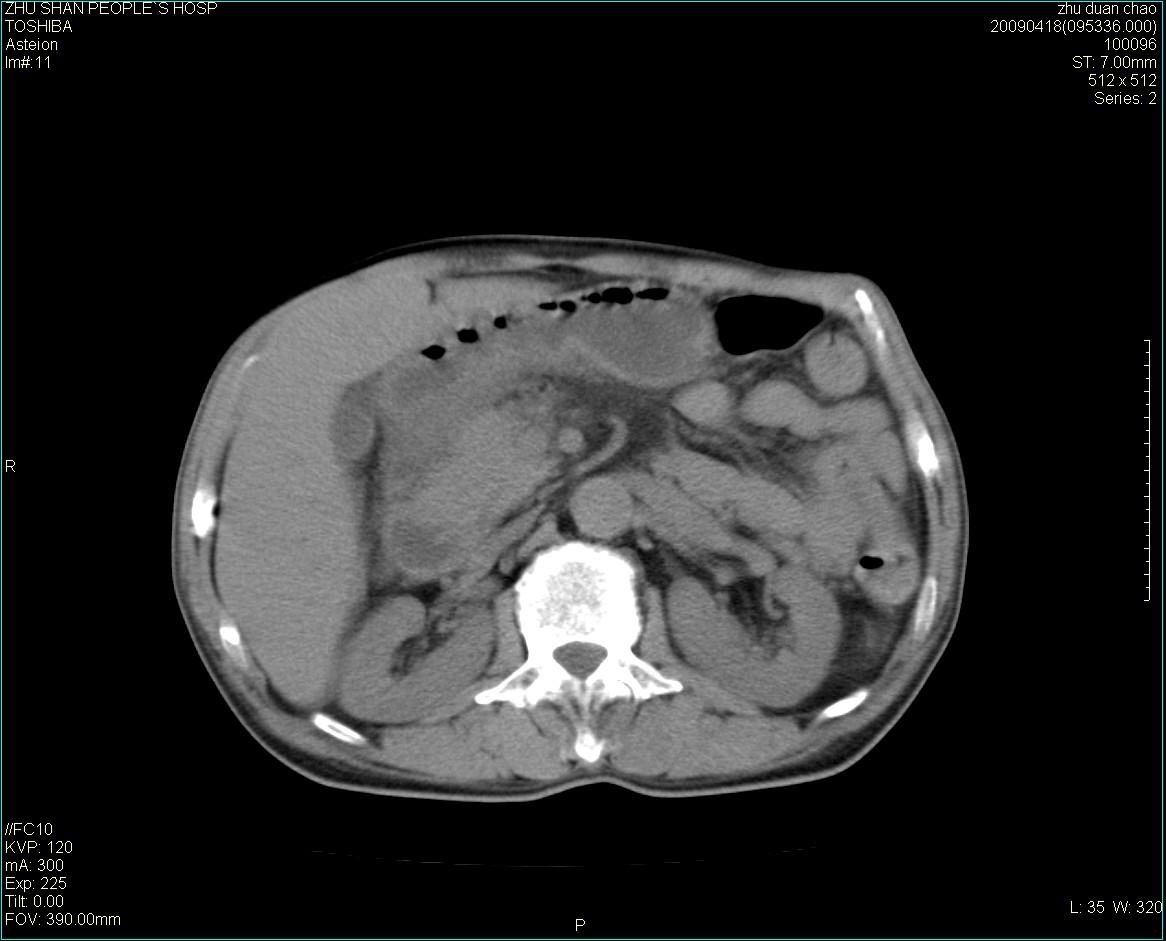

以下是引用余辉在2009-4-22 10:48:00的发言:[br]结肠肝曲附近肠段包块,病灶密度不均匀,周围肠系膜脂肪混浊,见多枚淋巴结肿大,考虑结肠癌可能性大,病灶累及范围较广建议进一步检查除外其他

以下是引用随光逐影在2009-4-22 11:57:00的发言:[br]考虑肠道肿瘤(间质瘤?)可能性大。

以下是引用ydx_74在2009-4-22 14:39:00的发言:[br]结肠癌周围侵犯可能,不能完全除外炎性病变